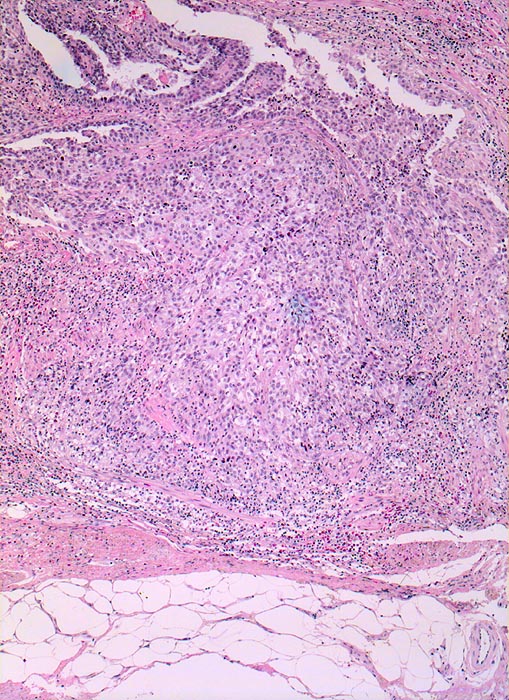

• Multiple Fragmente einer transurethralen Resektion.

• In der Mitte oben ist ein Harnblasenfragment mit tumorfreien Anteilen der Harnblasenwandmuskulatur erkennbar. Dieses Fragment ist bedeckt von einem aus wenigen Zellagen bestehenden dyskohäsiven Urothel, von dem sich einzelne Zellen ablösen. Die Zellkerne sind pleomorph, hyperchromatisch und vergrössert(Carcinoma in situ des tumorfernen Urothels).

• Fragmente eines papillär aufgebauten Karzinoms.

• Invasion der Lamina propria (Tumorfragmente links): Kleine Tumorzellgruppen oder Einzelzellen haben die Basalmembran an wenigen Stellen durchbrochen und liegen in der Lamina propria.

• Begleitendes dichtes gemischtes Entzündungsinfiltrat.